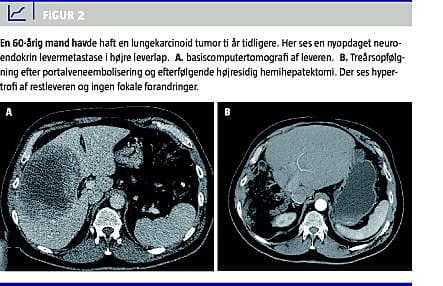

Den optimale behandling af patienter med malign sygdom i leveren er kurativt intenderet radikal resektion. Ved resektion skal der efterlades mindst 25% fungerende levervæv, for at leverinsufficiens kan undgås [1]. Selv om leveren har stor regenerationskapacitet, som påvist i dyreeksperimentelle studier, hvor man har reseceret leveren op til ni gange, uden at regenerationskapaciteten er blevet kompromitteret [1], vil den fremtidige leverrest (FLR) af og til være for lille til at kunne klare sufficient leverfunktion. Portal vene-embolisering (PVE) er en interventionsradiologisk behandling, der har til formål præoperativt at embolisere det portale kredsløb til leversegmenter med malignitet og derved ophæve den portale gennemblødning i disse og omdirigere den portale gennemstrømning til de raske og ikkeemboliserede segmenter. Herved opnås der hyperperfusion gennem den resterende uafficerede del af leveren (som regel venstre leverlap, segment 1, 2 og 3), og der opnås hypertrofi og øget volumen på omkring 30% af denne FLR [2, 3] (Figur 1 A + B). Dette muliggør ekstensiv leverresektion hos patienter, hvor der ellers var kontraindikation pga. af for lille leverrest [1]. PVE opfølges almindeligvis 3-6 uger senere af kirurgisk udvidet leverresektion af de tumorafficerede leversegmenter (almindeligvis højresidig hemihepatektomi med eller uden resektion af segment 4) på et tidspunkt, hvor den hypertrofierede leverlap har tilstrækkelig kapacitet til en sufficient leverfunktion [3]. Efter leverresektionen vil FLR yderligere kunne hypertrofiere med op til 38% [3] (Figur 2 A + B). PVE blev introduceret af Kinoshita et al i 1986 [4].